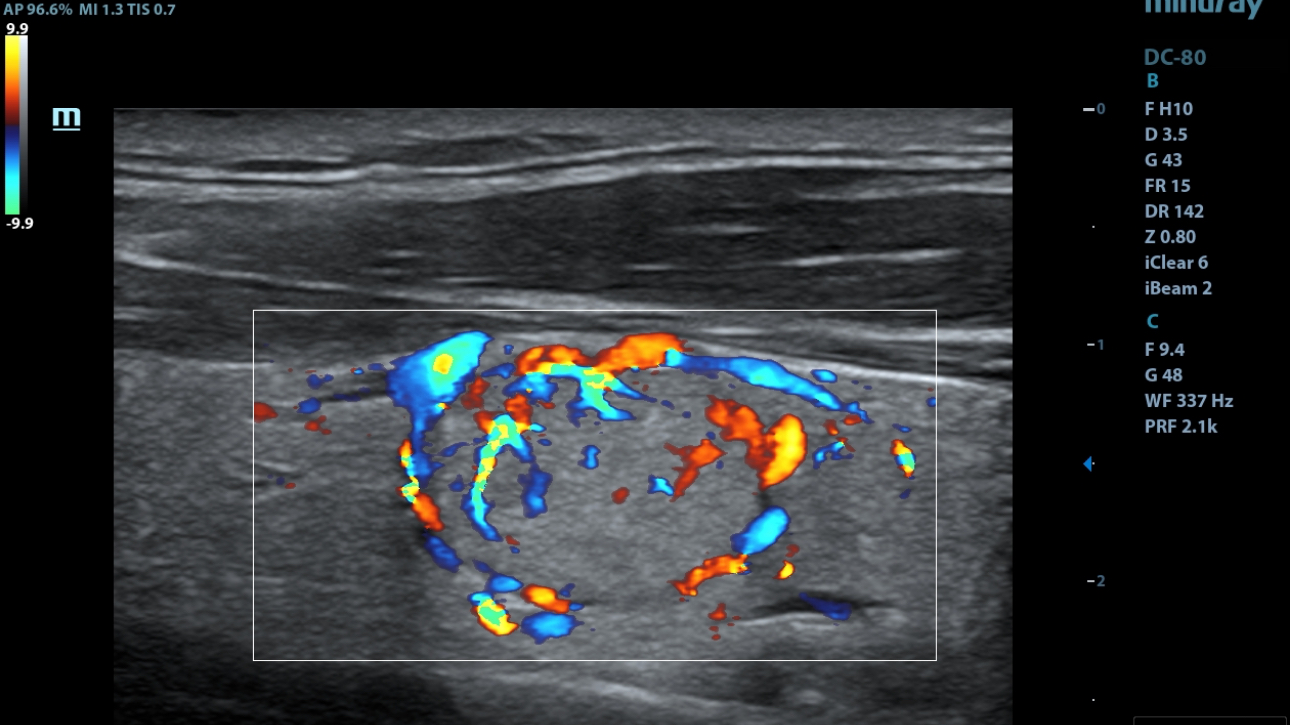

iNeedle

ItŌĆÖs the 2nd generation needle enhancement technology with automatic angle adjustments for easy needle approach to target and enhanced accuracy during guided procedures.

Smart Track

ItŌĆÖs Mindray unique feature to reduce repetitive, time-consuming scanning steps in vascular exams. Smart Track provides intelligent and real-time vessel tracking and real-time image optimization of Color and PW.